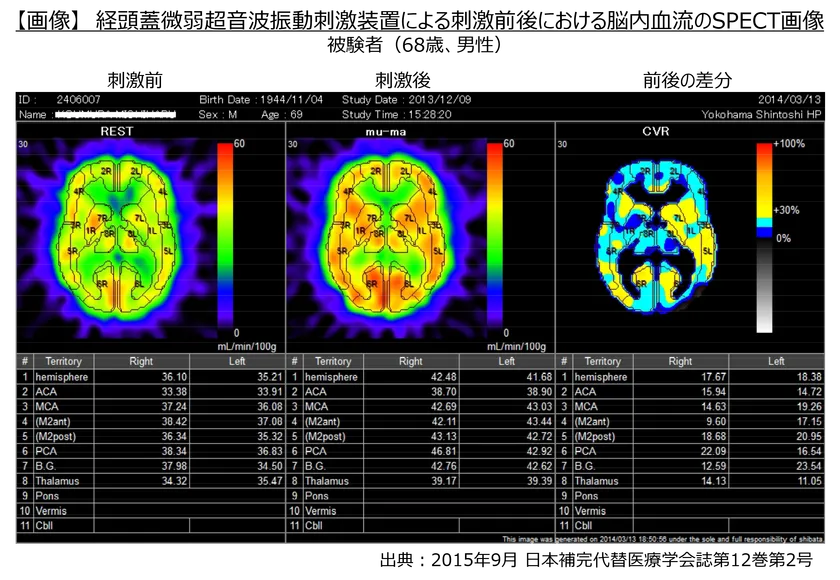

・その結果、イルカが発する30kHzの周波数帯で微弱な振動(2ミリワット/cm2以下)を初老期の健常人に20分間照射することにより脳血流が約15%増加したことが確認されました。

【画像】経頭蓋微弱超音波振動刺激装置による刺激前後における脳内血流のSPECT画像